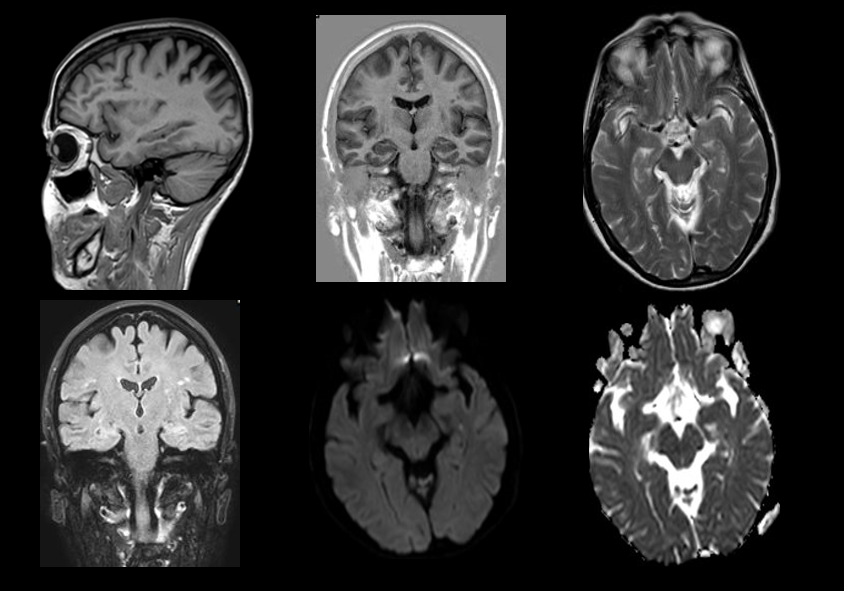

Secuencias de RM sin contraste intravenoso. En difusión se aprecia un foco de restricción puntiforme en hipocampo, que no se manifiesta en otras secuencias.

- Típicamente focos puntiformes que restringen en difusión localizados en hipocampo que suelen ser unilaterales y de predominio en lóbulo temporal izquierdo, aunque pueden ser bilaterales. En ocasiones pueden observarse como lesiones hiperintensas en las secuencias potenciadas en T2. Típicamente suelen desaparecer en control posteriores (>2 semanas).